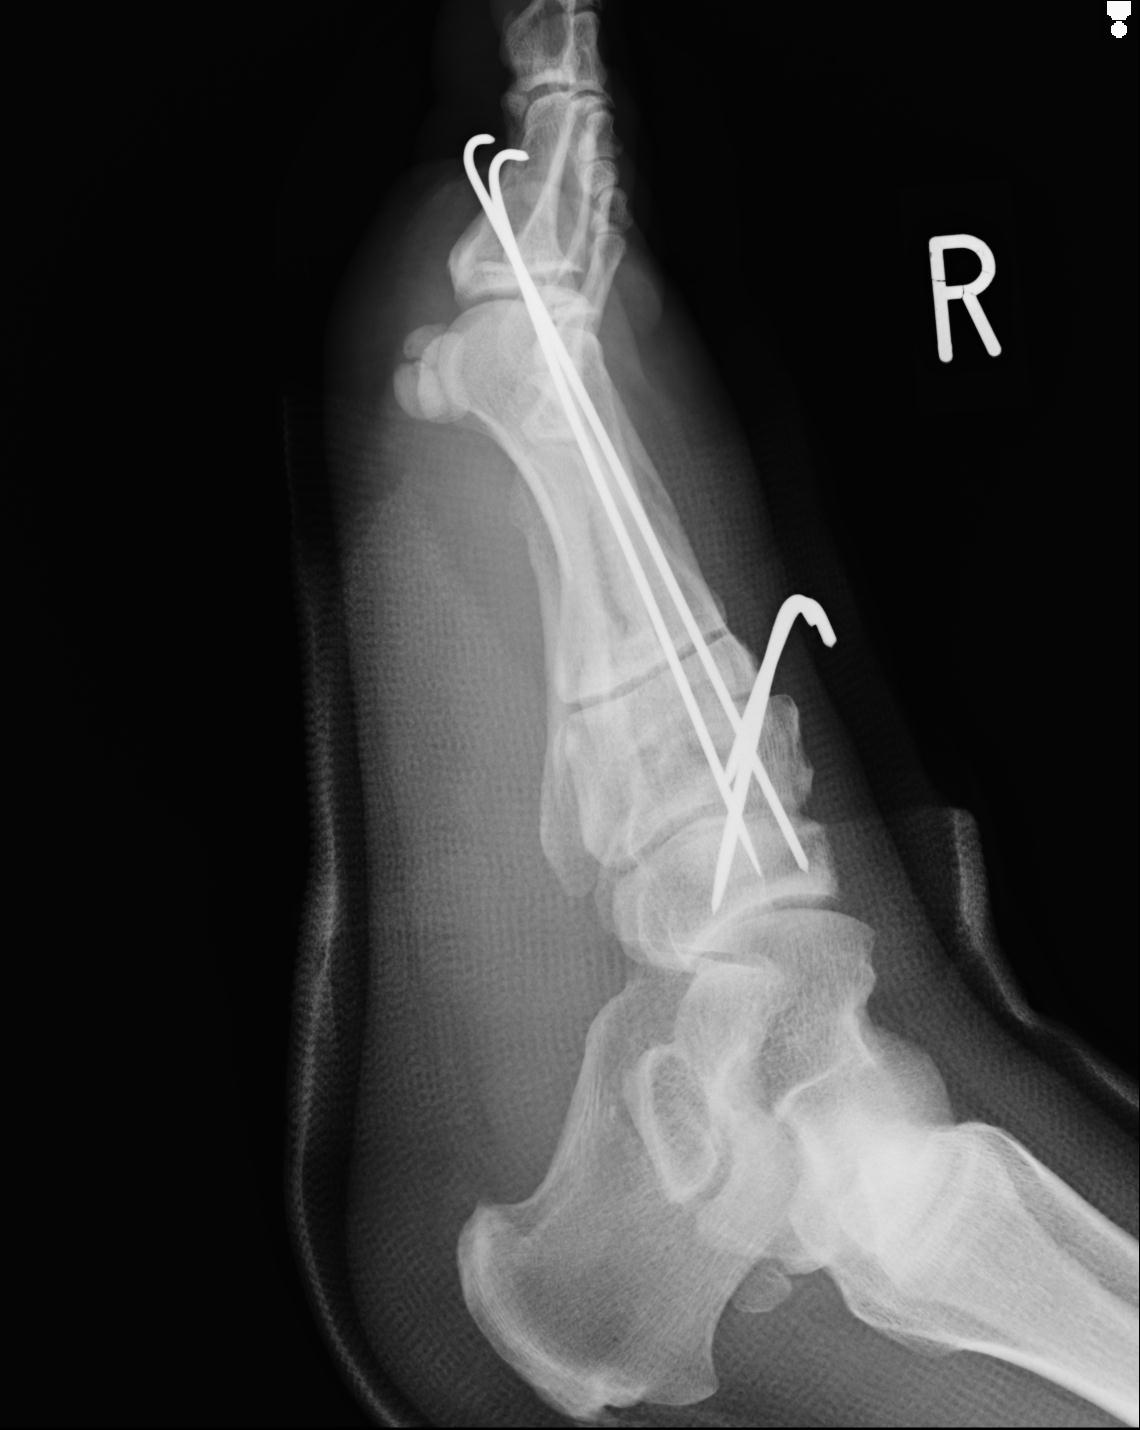

102755 1/4 2R 1/15 2R 右足関節 68歳女性 右三果脱臼骨折